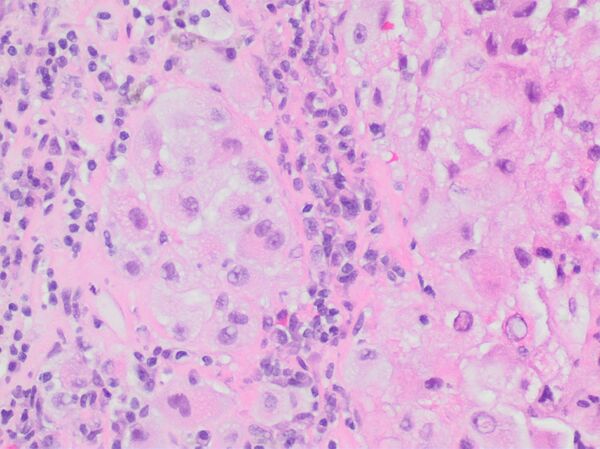

- Окончательный диагноз меланомы может быть установлен только после гистологического исследования, проведённого после тотального удаления невуса (опухоли) с достаточным захватом здоровых тканей. Предоперационная биопсия с помощью иглы или частичного удаления противопоказана, во избежание распространения меланомы. Определяется глубина прорастания (Clark, Breslow) и митотический индекс.

Клеточный состав меланомы не влияет на клиническое течение опухолевого процесса, однако такие признаки, как митотический индекс, уровень инвазии в дерму, изъязвление и некоторые другие, имеют прогностическое значение. Глубина инвазии меланомы остаётся лучшим прогностическим показателем. На этом основан расчёт пятилетней выживаемости больных с этим новообразованием (англ. Five Year Survival FYS).